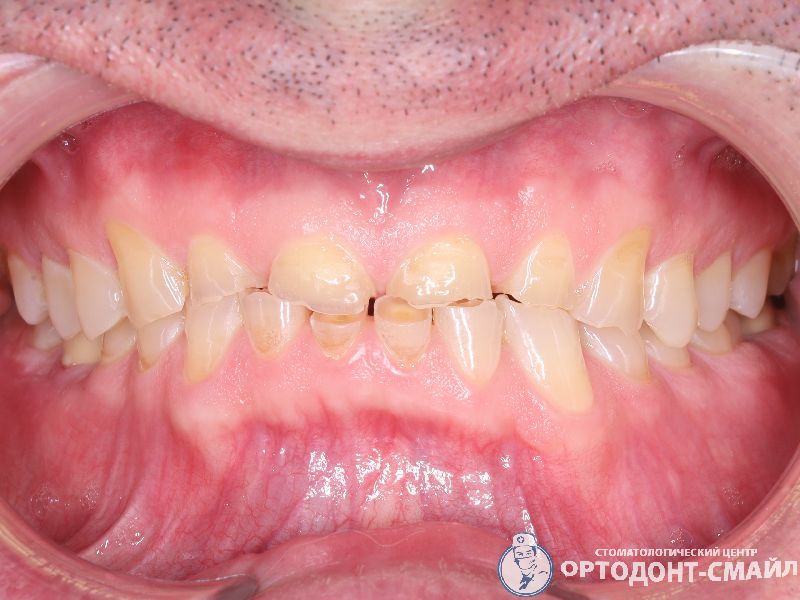

Диагноз: прямой травматический прикус, повышенная стираемость зубов.

Проведено: лечение ВНЧС, тотальная реабилитация по поднятию прикуса диоксидом циркона

вид спереди